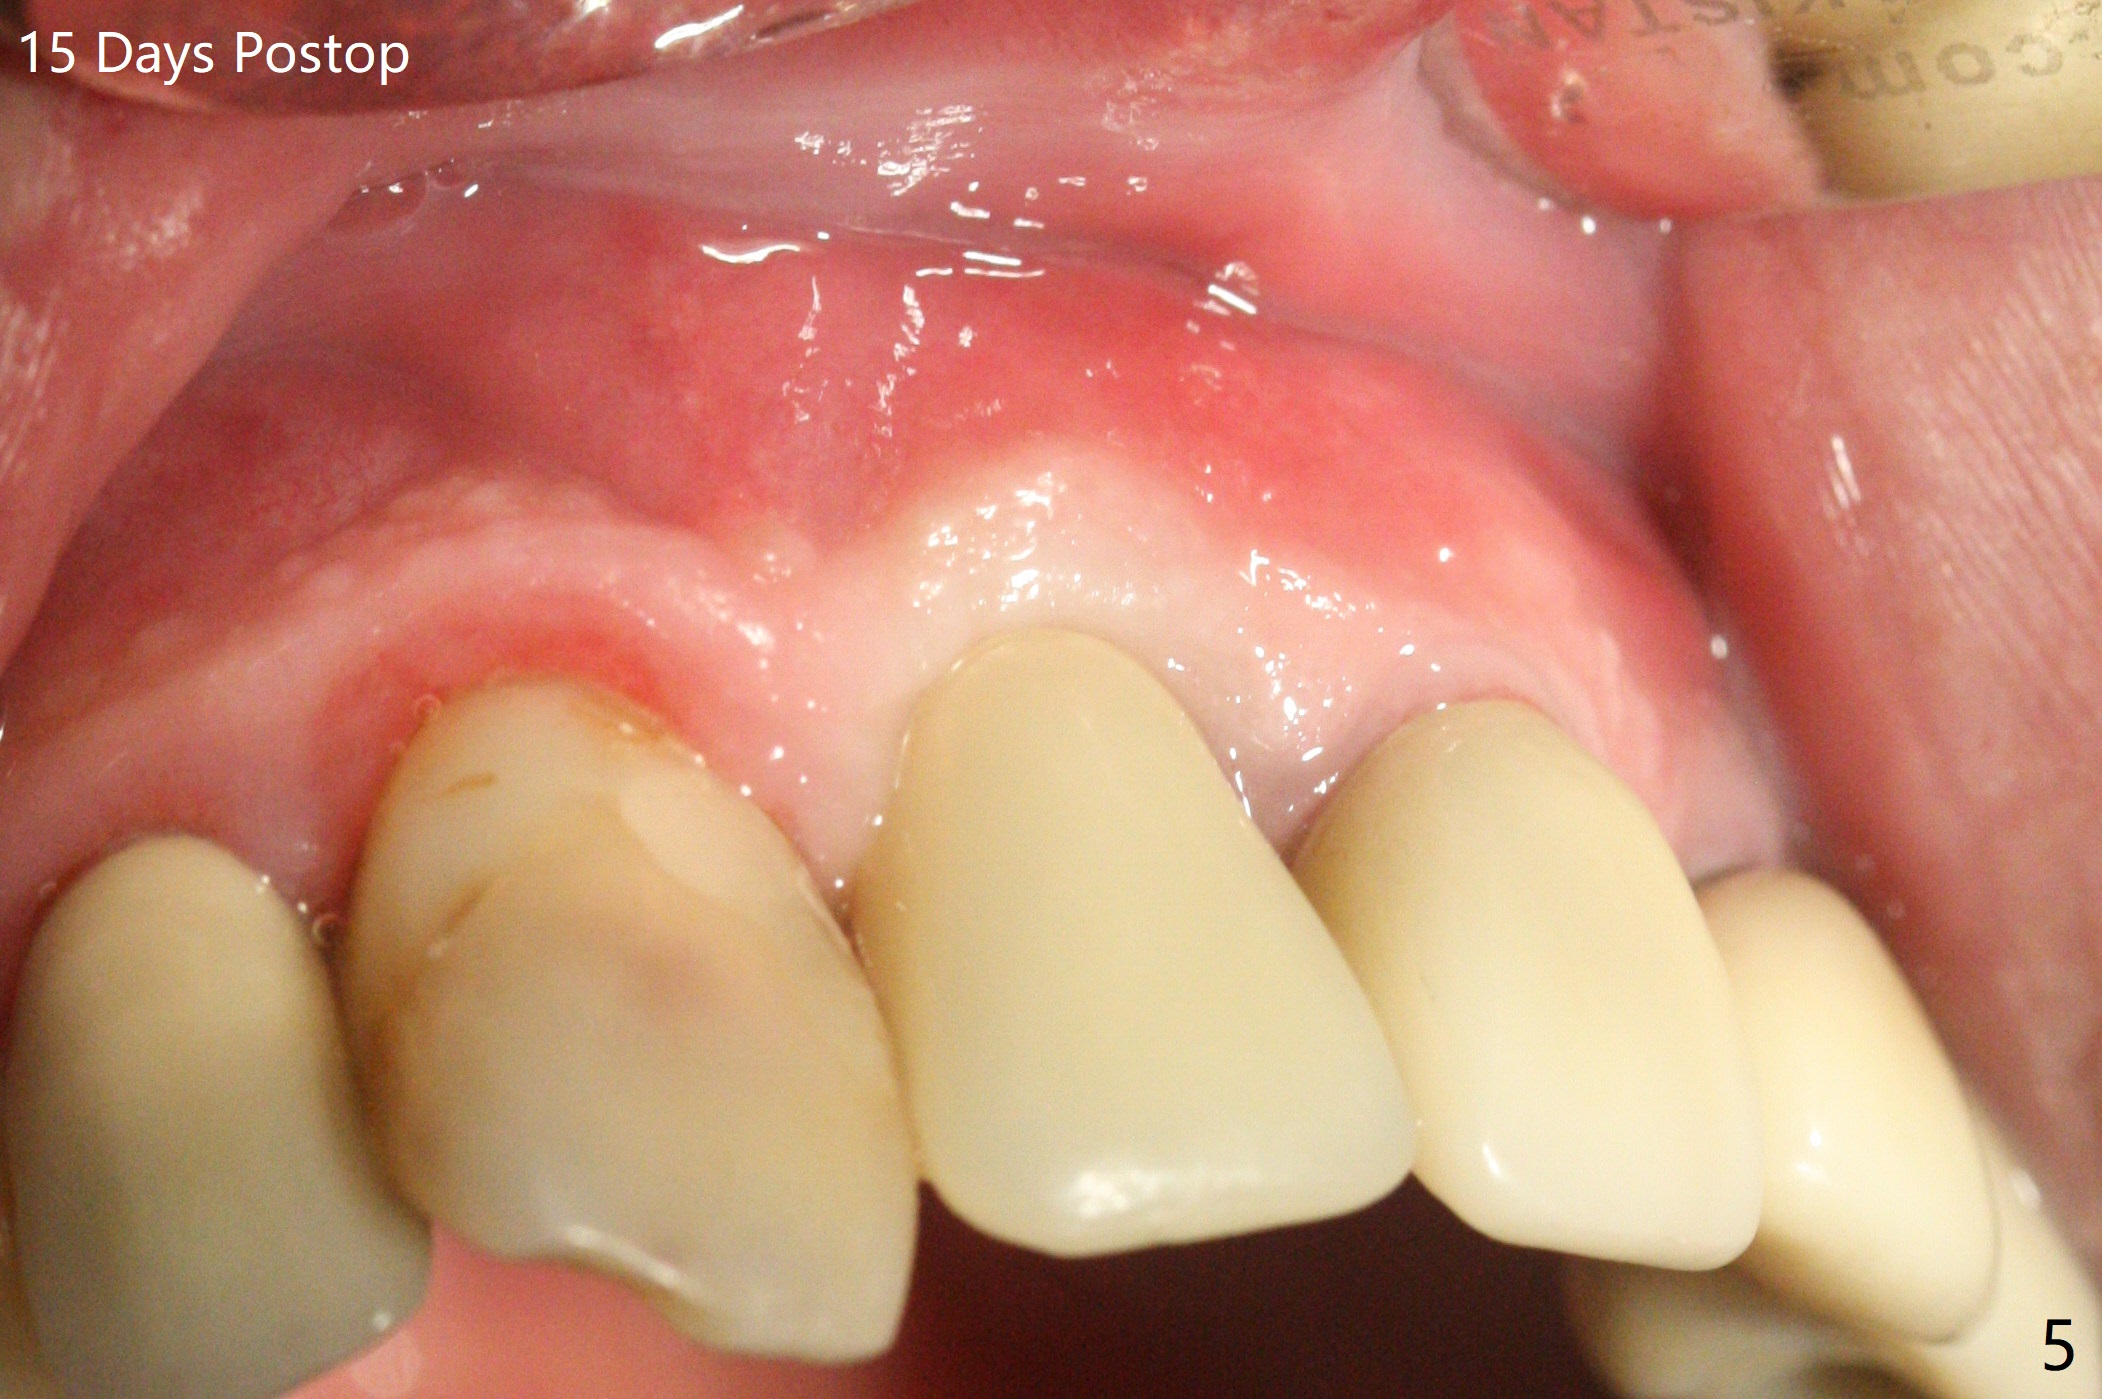

徒手种植不准确,需要反复调整,例如,为了避免接近侧切牙植体,中切牙钻洞开始于牙槽窝腭侧骨壁近中,结果接近切牙管(图一:红虚线),然后使用Lindamann bur移动钻洞,结果又太接近侧切牙(图二)。最后使用2毫米钻头试图改变钻洞方向,结果基台太接近侧切牙牙冠(图三)。而导板植入快,利索。 植入皮质骨骨粉(图四:*)后,制作临时牙冠。大约术后11天临时牙冠脱落(可能基台太短),病人没有及时复位,4天后牙槽窝愈合,可能变小,牙冠就位有些困难,造成颊侧牙龈发白(图五)。一周后牙冠又脱落,衬里后(图六:*)颊侧牙龈又显得饱满。